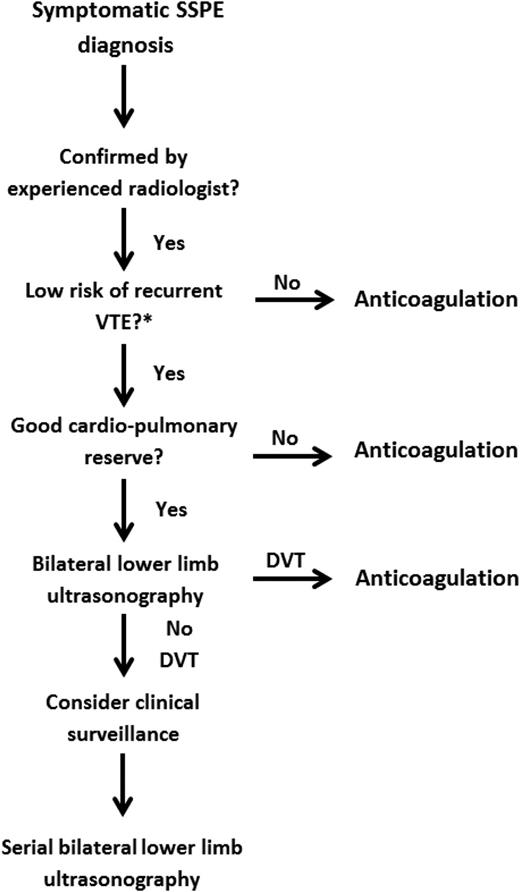

Although the clinical importance of SSPE remains debatable, it is important to establish a safe management strategy on a case-by-case basis that accounts for the risk of recurrent VTE and bleeding episodes and patient preference (see Figure 2). If a decision is made to not initiate anticoagulant therapy in patients with isolated SSPE, clinicians must have a standardized approach to manage these patients safely (Figure 2).

Management strategy for symptomatic subsegmental pulmonary embolism. DVT, deep vein thrombosis; SSPE, subsegmental pulmonary embolism; VTE, venous thromboembolism.

Management strategy for symptomatic subsegmental pulmonary embolism. DVT, deep vein thrombosis; SSPE, subsegmental pulmonary embolism; VTE, venous thromboembolism.

A recently published Cochrane review failed to identify any randomized controlled trials to guide clinicians on the management of patients with SSPE.19 Therefore, physicians have to rely on clinical data from other patient populations, including those with suspected PE or a larger PE burden. SSPEs were previously shown to be frequent among patients with suspected PE and nondiagnostic V/Q scans. In the Prospective Evaluation of Pulmonary Embolism Diagnosis (PIOPED) study, 17% of patients with a low probability V/Q scan had SSPE on pulmonary angiography.20 Therefore, it is probably reasonable to presume that many patients with SSPE on multirow CTPA would have had a nondiagnostic VQ scan. Over the last decades, many prospective management studies have shown that patients with suspected PE and nondiagnostic V/Q scans can be safely managed without the use of anticoagulant therapy, provided that there is no DVT in the lower extremities.21-23 Similarly to patients with nondiagnostic VQ scans, patients with SSPE without DVT on lower limb ultrasonography might be managed conservatively without anticoagulant therapy. It is particularly important to rule out DVT in patients with SSPE, given that rates of concomitant proximal lower limb DVT have been reported at 7.1% (95% CI, 1.2% to 31.5%) in this patient population.24

This is consistent with the 2016 American College of Chest Physicians (ACCP) clinical practice guideline, which suggests using clinical surveillance instead of anticoagulation for patients with SSPE and no proximal DVT in the legs who have a low risk of recurrent VTE (grade 2C).25 Clinical surveillance should be supplemented by serial ultrasonography of the lower extremities within 5 to 7 days. Clinicians might want to favor this treatment option if the patient has good cardiopulmonary reserve or has a high risk of bleeding. However, if patients have a high risk of recurrent VTE, the latest version of the ACCP guidelines suggests anticoagulation therapy over clinical surveillance (grade 2C). Numerous risk factors for recurrent VTE have been proposed to help guide clinicians on stratifying the underlying risk of recurrent VTE. These risk factors include hospitalization, immobility, active cancer (especially metastatic disease or ongoing chemotherapy), or an unprovoked event.25 Similarly, the European Society of Cardiology clinical practice guideline suggests that an individualized approach be taken after careful assessment of the risk/benefit ratio for patients with isolated SSPE and negative leg ultrasonography results.26 Therefore, serial ultrasonography of the lower extremities might be a reasonable alternative to anticoagulation in low-risk patients.